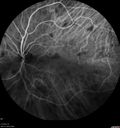

66 year old man with dense cataracts and recurrent uveitis. Starting 6 days ago and before that New Years Eve. The left eye has been treated since 11/2013 for iritis in the left eye. The patient was on Prednisolone drops. He weaned down completely off the drops and he was fine until New Years. He restarted the drops and the vision cleared until last Saturday. The attack was usual. He gets a lot of pain in the left eye and the eye is sensitive to the touch. His vision gets a little worse with the attacks. He has had episodes in each eye. He has a history of severe intermittent right knee pain and also has ulcers on his lower leg on both sides which are thought to be circulatory. VA OD: Dcc20/40 PH20/32-2 VA OS: Dcc20/200-2 PH20/63-1 Syphillis, Sarcoid, TB, Birdshot Negative except for slightly elevated Lysozyme and normal ACE Dentist found cyst which was biopsy positive for sarcoid 6 months later.

Sarcoidosis Multifocal Choroiditis580 views66 year old man with dense cataracts and recurrent uveitis. Images show multifocal choroidal granulomas from sarcoidosis more in the right eye than the left eye.00000